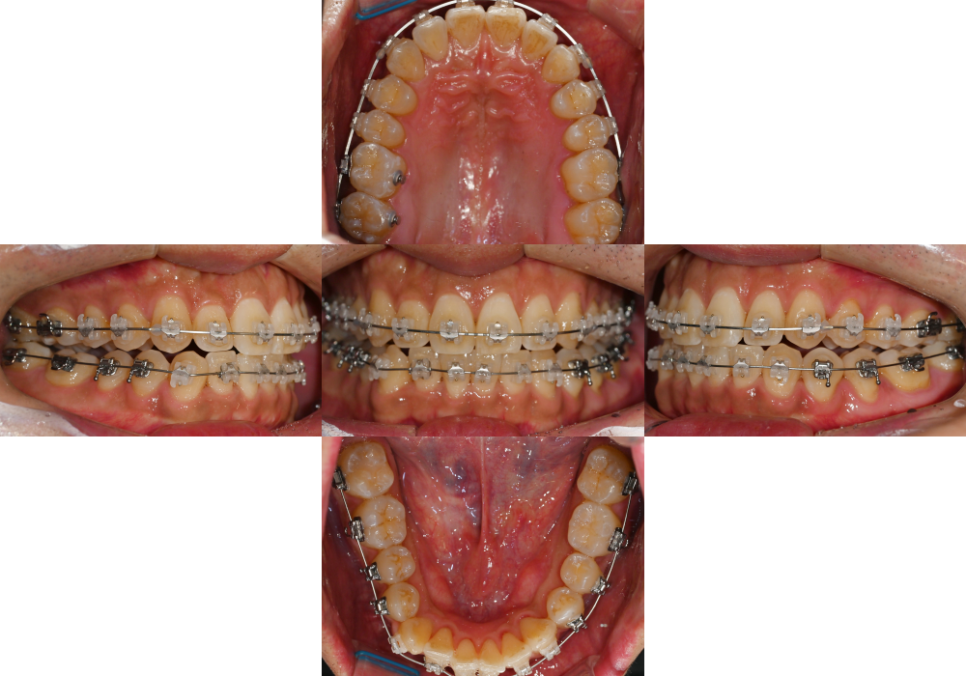

24.03.23

브라켓을 부착한 뒤

정확한 치아 맞물림을 위해

위턱 오른쪽 구치부에 버튼을 부착한 것을

보실 수 있습니다.